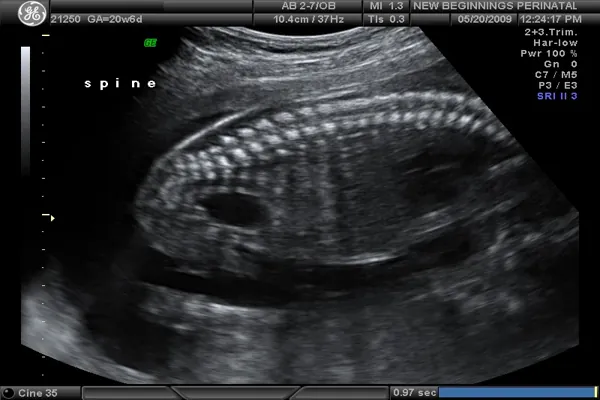

معاینه اولتراسوند: در طول سونوگرافی بیوفیزیکال ، روی تخت معاینه دراز کشیده اید. ارائه دهنده دستگاهی به نام مبدل (یا پروب) را روی شکم شما حرکت می دهد تا امواج صوتی تولید کند. مبدل امواج صوتی را به تصاویری تبدیل می کند که می توان آن ها را روی صفحه نمایش مشاهده کرد.

تست بدون استرس NST: در حالی که روی تخت دراز کشیده اید برای سونوگرافی بیوفیزیکال ، یک مانیتور الکترونیکی، ضربان قلب جنین را اندازه گیری می کند.